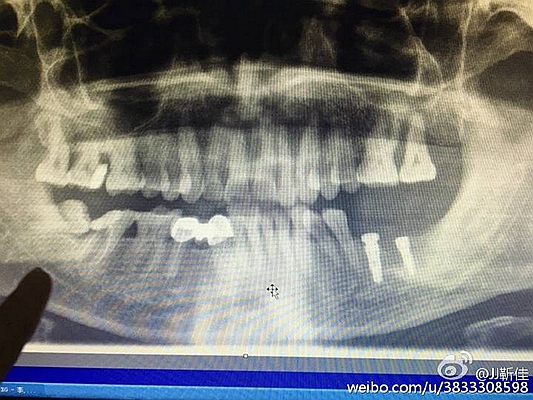

2016.8.3涉縣美康口腔王主任種植牙于額外牙拔除

左下67缺失

ct定位

術(shù)后拍片